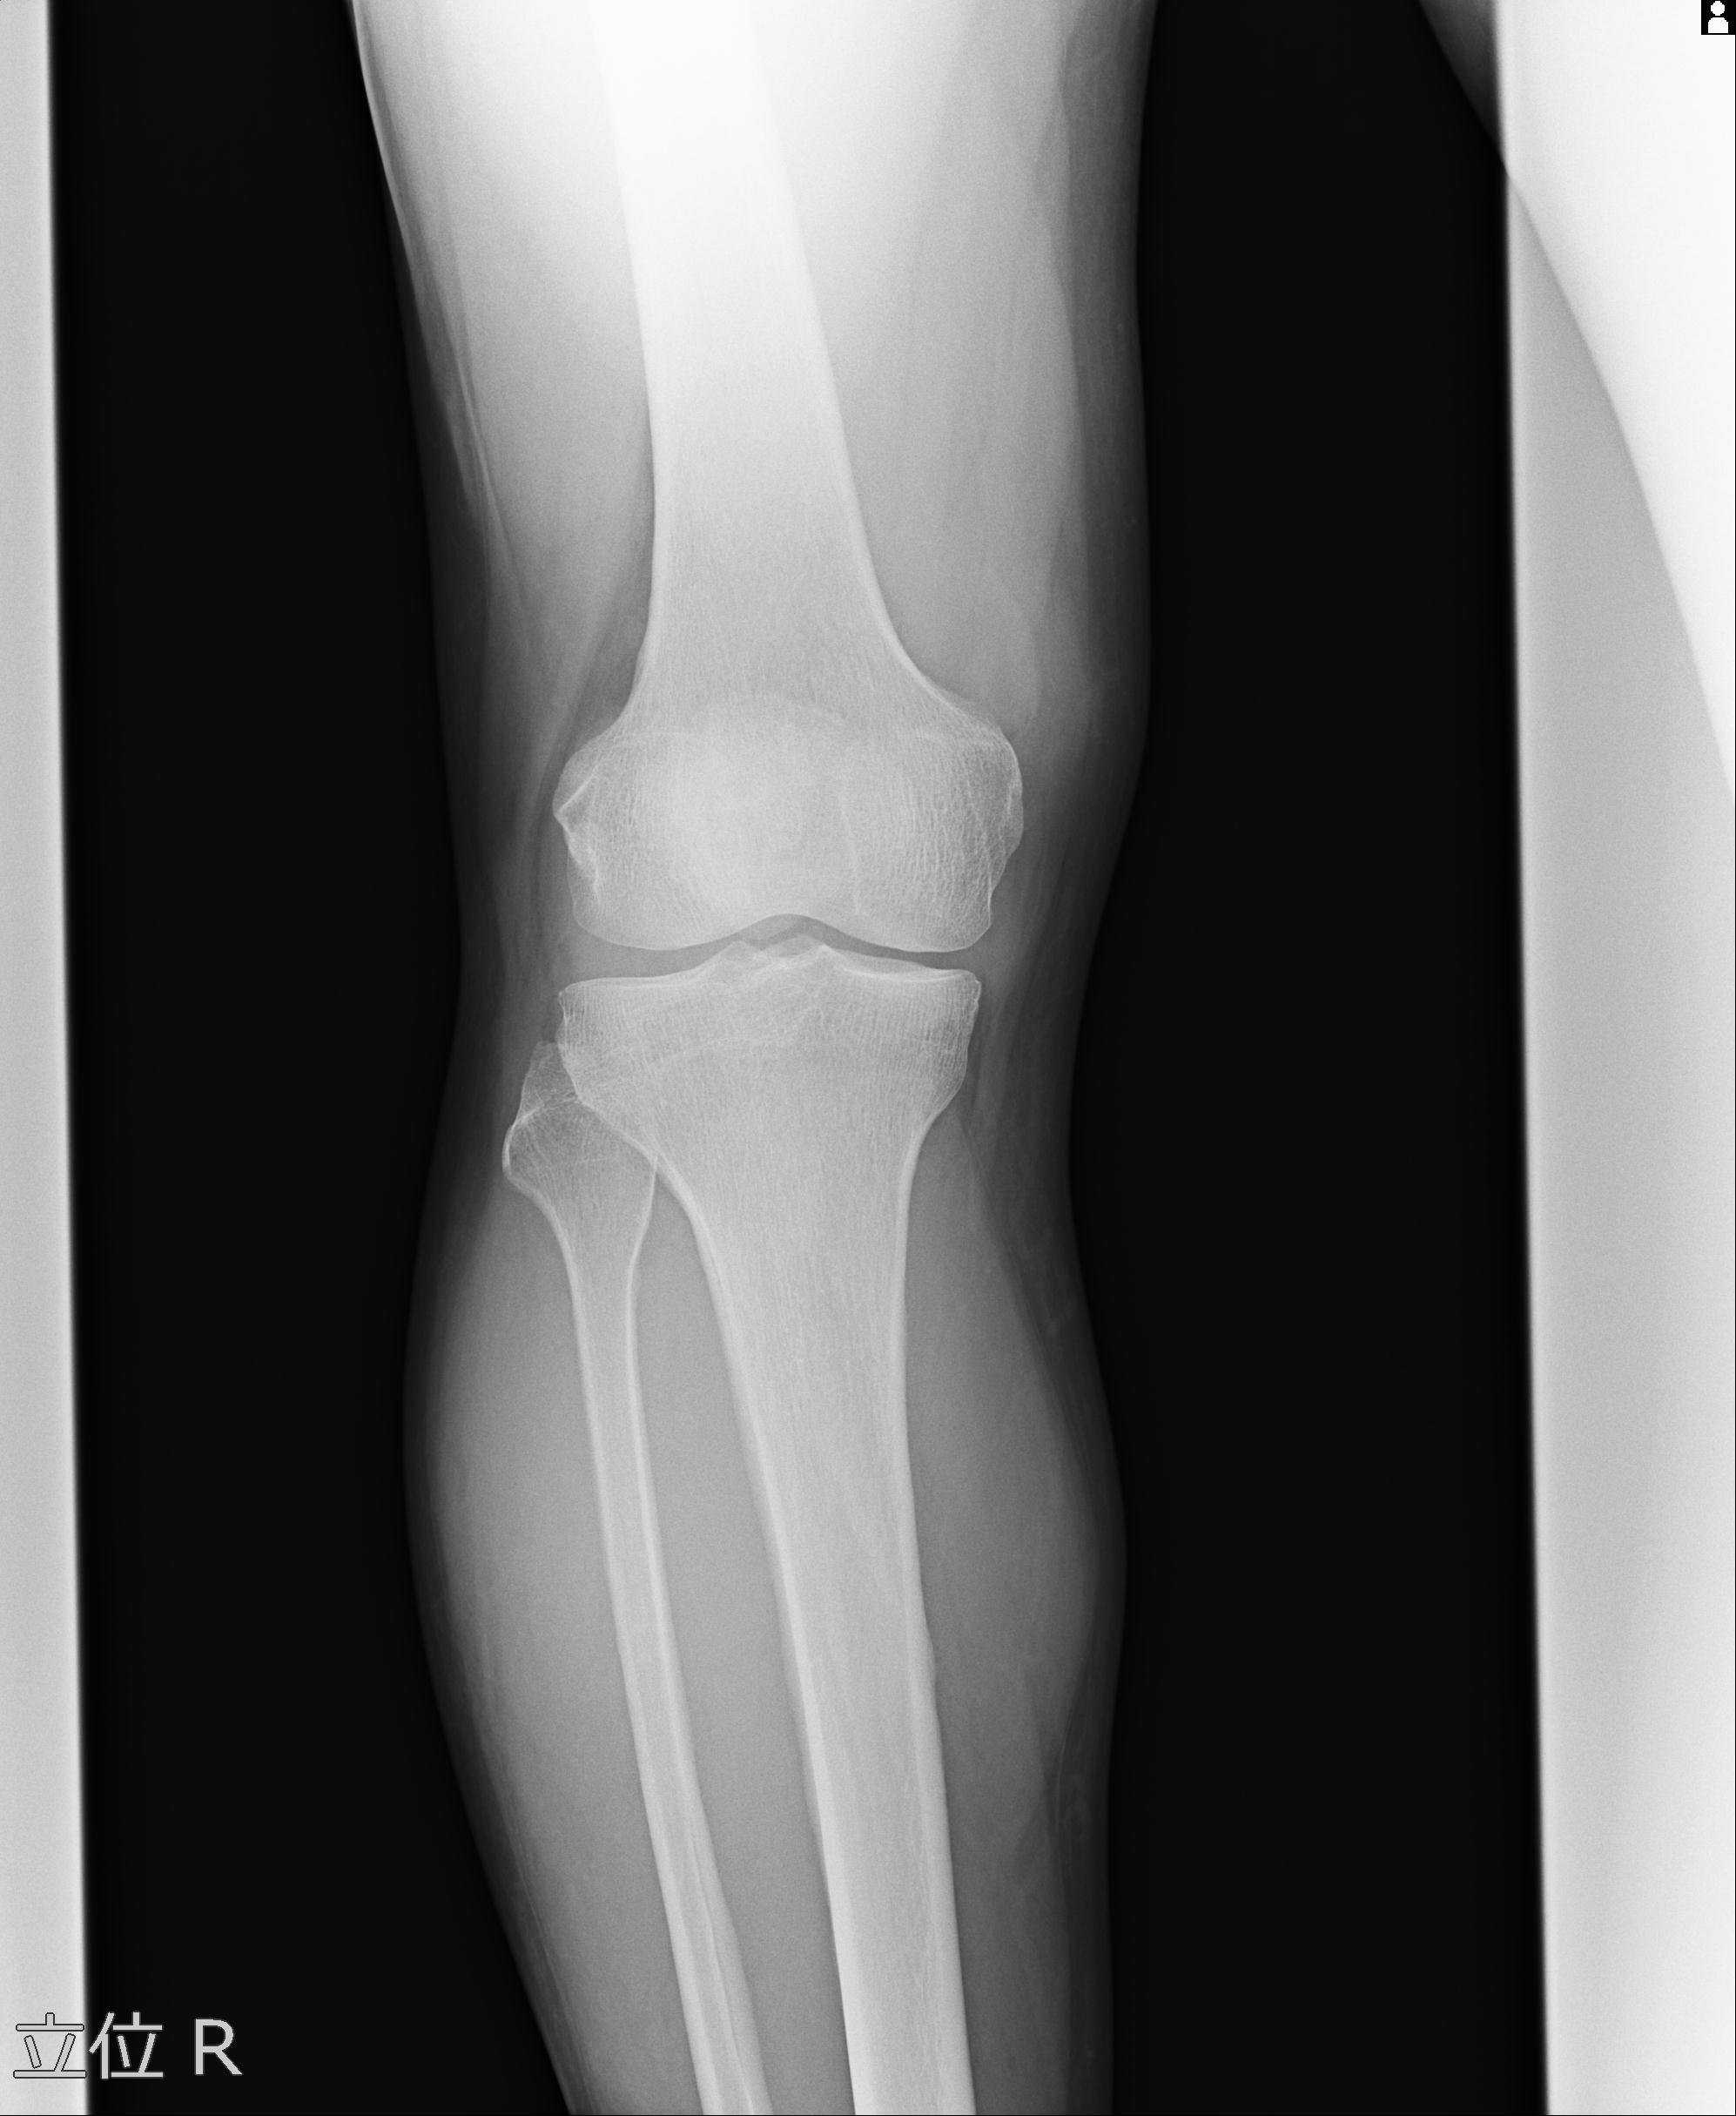

49554 3/13 膝 4R 3/16 4R 1/18 2R 78歳男性 膝蓋骨骨折

100612 11/25 1/20 右膝 2R 84歳女性 右TKA

91983 11/16 左膝 2R 11/18 2R 55歳男性 脛骨骨切り術